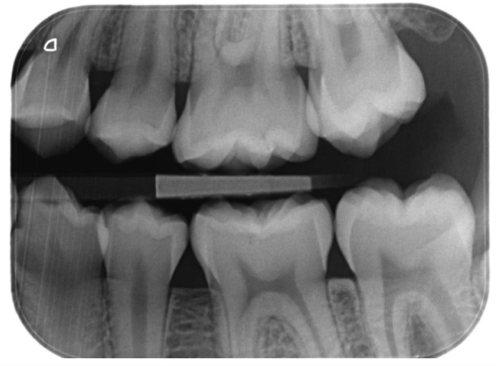

Beskriv fejl på billedet

Er optagelsen ortoradial? Begrund dit svar

Vurdér optisk densitet på denne optagelse

Hvilke tænder ser du på billedet?

Hvordan vil du vurdere kontrasten på denne optagelse? Begrund dir svar.

Forklar hvad det betyder at denne røntgenoptagelse er et summationsbillede.

De strukturer vi røntgen fotograferer er 3 dimensionale, disse strukturer gennemtrænges af røntgenstrålerne/fotonerne og energien af de røntgenstråler der er nået igennem strukturen summeres på en billedmodtager (analog film, fosforplade, sensor) og der fremstilles et 2 dimensionalt billede.